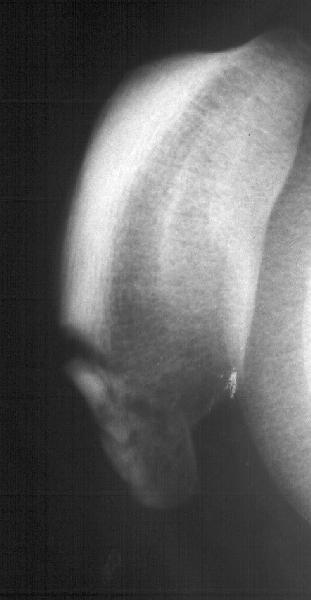

Мужчина 33 лет поступил через 2 недели после автоаварии (был за рулем) с переломом бедра. На этой же стороне есть перелом нижнего полюса надколенника. Клинически отека и гемартроза нет, интенсивная пальпация слабо болезненна прямо над линией перелома. Пальпаторно разгибательный аппарат сохранен. Бедро вчера синтезировано стержнем. Сделал сразу после этого снимок в полном сгибании - ничего никуда не расходится, и у меня рука не поднялась. Есть ли настоятельная необходимость оперативной фиксации, и если да, то чем?

since the fracture does not involve the articular surface and the q mechanism is intact, I agree you have done the right thing in not operating on it. As the fr is not displacing even in full flexion you may treat the patient as if e has no patellar fracture!